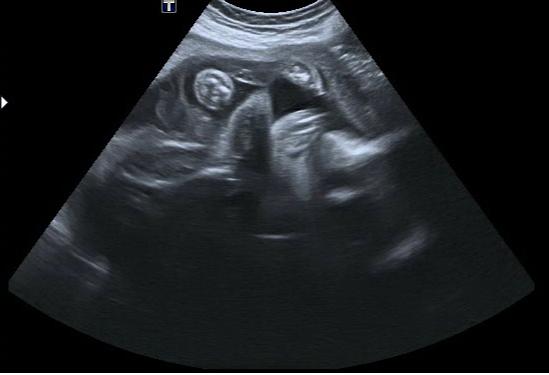

Je to holčička nebo chlapeček? Foto ultrazvuku

Ahoj maminky a budoucí maminky 😉 Prosím, poradila byste mi některá, co vidíte na fotce z ultrazvuku ve 20. týdnu za pohlaví? Určitě jste foteček viděly už mraky, proto vás žádám o radu...Nechci nikoho ovlivnit, proto svůj tip řeknu později 🙂 Děkuju moc!!!

Holčičku bychom tááák moc chtěli, ale jednou asi v 17. tt nám řekli, že to vypadá na chlapečka a teď ve 21. týdnu zas prý na holčičku, ale že by to chtělo ještě jednou potvrdit...

Nu, vidím také holčičku a to, co se jeví jako pinďa mi připadá takové nějaké zatočené, že mi to přijde spíš jako pupečník... 😉 Jinak co se týče osy zadečku a kávového zrna - tak to je v jedné ose - je to vidět, že zadeček je mírně na stranu a s ním i osa kávového zrna 😉

dle mne holčička 😉

Fotečka mi z počátku nedala spát, protože tam vidím něco navíc čouhat 🙂

A lékařů názor, pokaždé jiný.